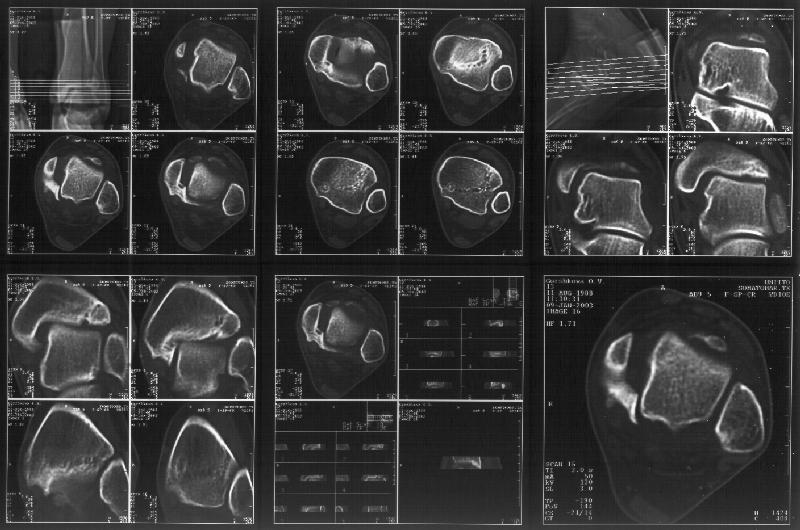

Re: Последствия травмы голеностопного сустава

I attach CT of the affected ankle.